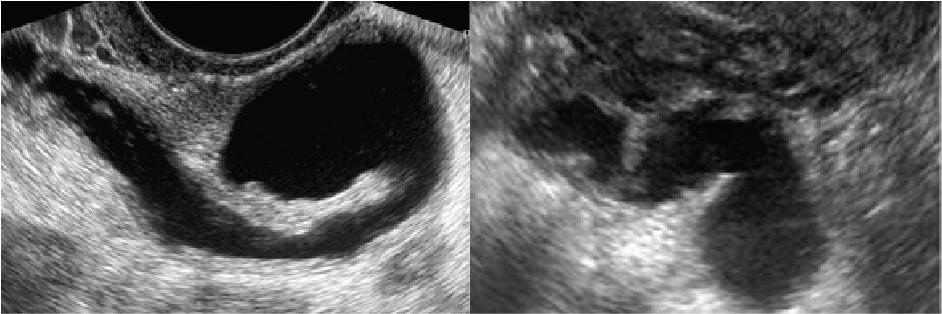

Thực tế, Siêu âm có phát hiện tắc vòi trứng không phụ thuộc vào tình trạng cụ thể. Siêu âm thường chỉ thấy được Hình ảnh ứ dịch vòi trứng (khi vòi trứng sưng to chứa dịch). Để chẩn đoán chính xác vòi trứng có thông hay không, bác sĩ bắt buộc phải chỉ định chụp tử cung vòi trứng (HSG).

Thông qua Hình ảnh ứ dịch vòi trứng trên siêu âm đầu dò hoặc chụp HSG, bác sĩ sẽ đánh giá mức độ nghiêm trọng.